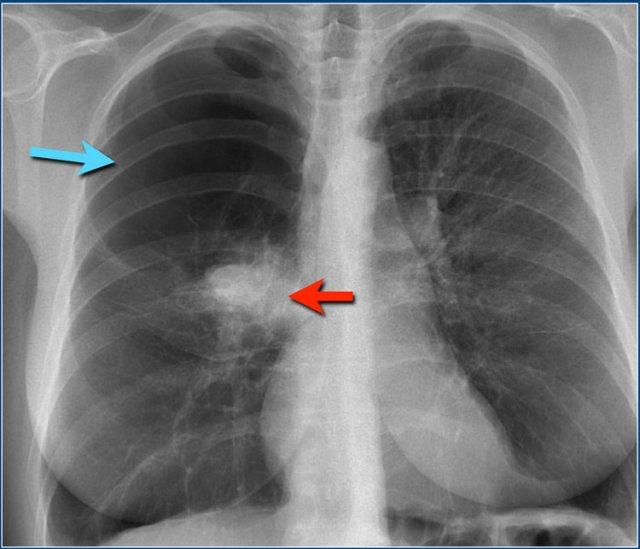

Đây là hình ảnh đông đặc thùy điển hình.

Hãy quan sát kỹ hình ảnh trước, sau đó tiếp tục đọc.

Các dấu hiệu bao gồm:

- Tăng tỷ trọng với bờ không rõ ở phổi trái

- Bóng tim vẫn còn nhìn thấy, điều này có nghĩa là vùng tăng tỷ trọng nằm ở thùy dưới

- Dấu hiệu khí phế quản đồ

Khi các phế nang bao quanh phế quản trở nên đặc hơn, phế quản sẽ trở nên rõ hơn, tạo ra dấu hiệu khí phế quản đồ (mũi tên).

Trên X-quang ngực có vùng tăng tỷ trọng bờ không rõ ở thùy trên phổi phải mà không có mất thể tích.

Rốn phổi phải ở vị trí bình thường.

Lưu ý dấu hiệu khí phế quản đồ (mũi tên).

Trong bối cảnh lâm sàng phù hợp, đây rất có thể là viêm phổi thùy hoặc phân thùy.

Tuy nhiên, nếu bệnh nhân này có sụt cân hoặc triệu chứng kéo dài, chúng ta cần đưa vào danh sách các nguyên nhân gây đông đặc mạn tính.

Đây là trường hợp viêm phổi thùy cấp tính do Streptococcus pneumoniae.